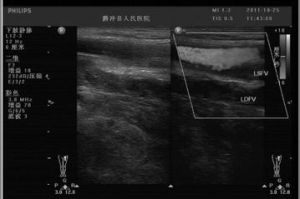

譜線增寬 正文 配圖 相關連線寬處的肝包膜(包 括尾狀葉),測 量其最大前後距離,左時長度測量點分別...第一肝門1-2c m處測量其寬徑,膽總管 測量要求在其全長之最寬處測量...膽囊體的最寬徑。正常值:通常小於3.5cm。 3.膽囊壁厚徑:正常值...